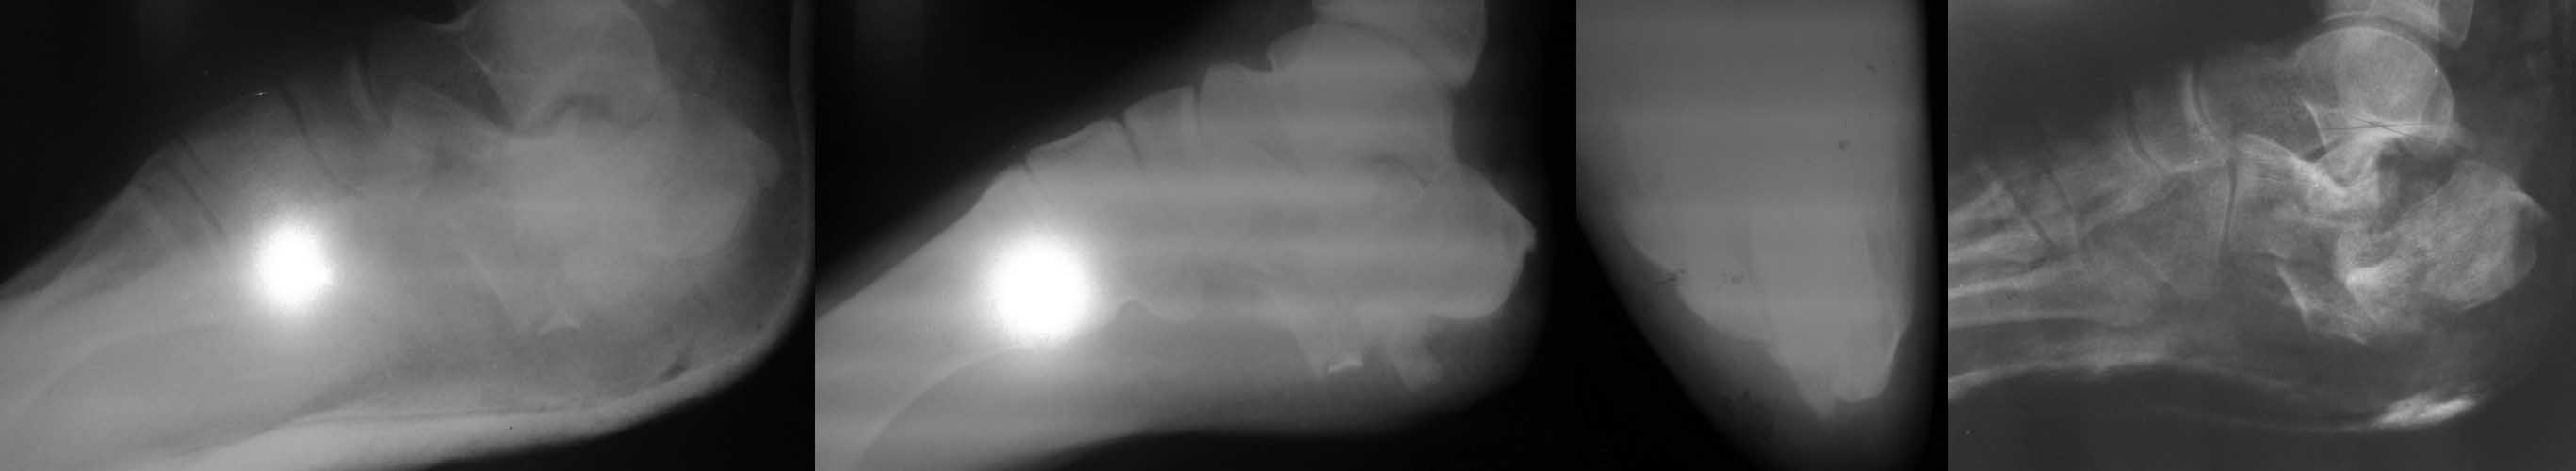

Уважаемые коллеги! П-ка, 28 лет, выпрыгнула с 3 этажа в состоянии а/о, неосл.переломы L1,2,3,ушиб почки, мочевого пузыря, перелом пяточной кости справа без смещения, оскольчатый перелом левой пяточной кости со смещением. Rn-гр.соответственно при поступлении, контроль в динамике и после закрытой ручной репозиции под в/в анестезией. Грубое смещение сохраняется. В арсенале спицы Киршнера, возможен забор аутотрансплантата. Есть сомнения по поводу заживления (алкогольный анамнез и возможно не только) после операции. Нужно в данном случае всеми средствами приводить к более менее терпимой картине? Допустима операция после консолидации этой "каши" в отсроченном порядке или вообще консервативная тактика. Повторюсь, есть сомнения в выполнении п-кой послеоперационных рекомендаций, возможно нарушение ортопедического режима? Спасибо за ваше мнение.

По представленным рентгенограммам судить о чем-то сложно. Полноценным исследованием считается с выполнением снимков в 5 проекциях, а лучше еще и КТ. По латеральной проекции после репозиции создается впечатление об относительно приемлемом состоянии подтаранного сустава. Возможно, в данной ситуации после спадения отека (появление морщинок на коже стопы) можно попробовать отрепонировать бугор пяточной кости на стержне Штеймана, фиксировать спицами, проведенными через него в таранную и кубовидную кости, загнув и оставив их над поверхностью кожи. Иммобилизация окончатой повязкой. Спицы, кстати, уменьшат желание ходить на сломанной пятке. Если пациентка совсем не комплаентна, можно оставить как есть с прицелом на артродез подтаранного сустава через год-два, если созреет. Открыто оперировать не стал бы в силу интеллектуально-социальных особенностей пациента, даже если бы ORIF была бы показана по рентгенограммам и КТ.